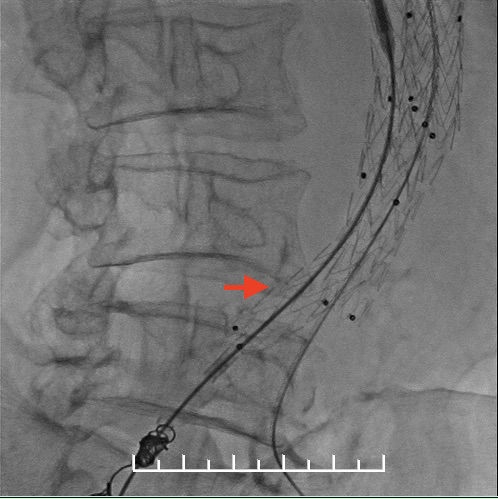

左股动脉入路导丝超选短腿失败,经右侧肱动脉使用导丝穿针引线从股动脉引出。

左侧髂动脉送入支架困难,但难不倒我们。

左右分别使用13.5*80、13.5*60mmFluency延长。左侧支架一定要越过髂动脉弯曲处,否则容易闭塞。此处可以看到左侧支架远端稍微有弯曲折叠。